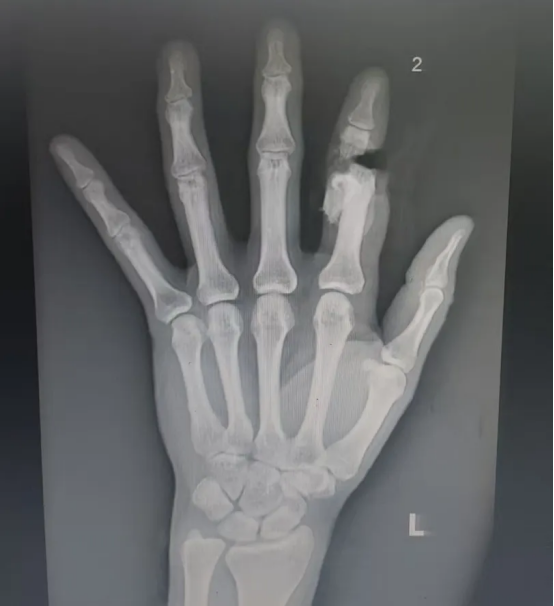

术后摄片

当止血带松开,原本苍白的指尖逐渐恢复红润,皮温与毛细血管反应恢复正常——标志着断指血运成功重建!术后,医护团队加强对患者的抗感染、镇痛治疗等,吴女士再植手指血运持续良好。